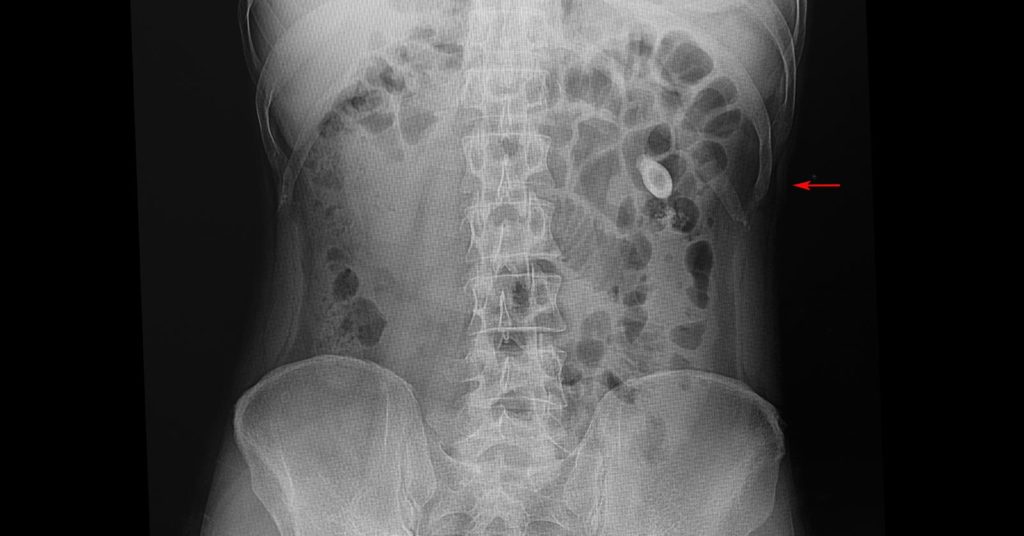

Sometimes, kidney stones can be as small as a grain of sand but some bigger stones can cause trouble in your urine flow along with a lot of pain. In some cases, treatment may be required to break down the stones or remove the ones that don’t pass. (Healthline, 2017) Passing a kidney stone can be painful, but if diagnosed in time, it does not cause a lot of damage.

Smaller kidney stones generally do not have any symptoms unless it moves around in your kidneys or passes into your ureters, the tubes that connect your kidneys to the bladder. Certain symptoms of kidney stones are: